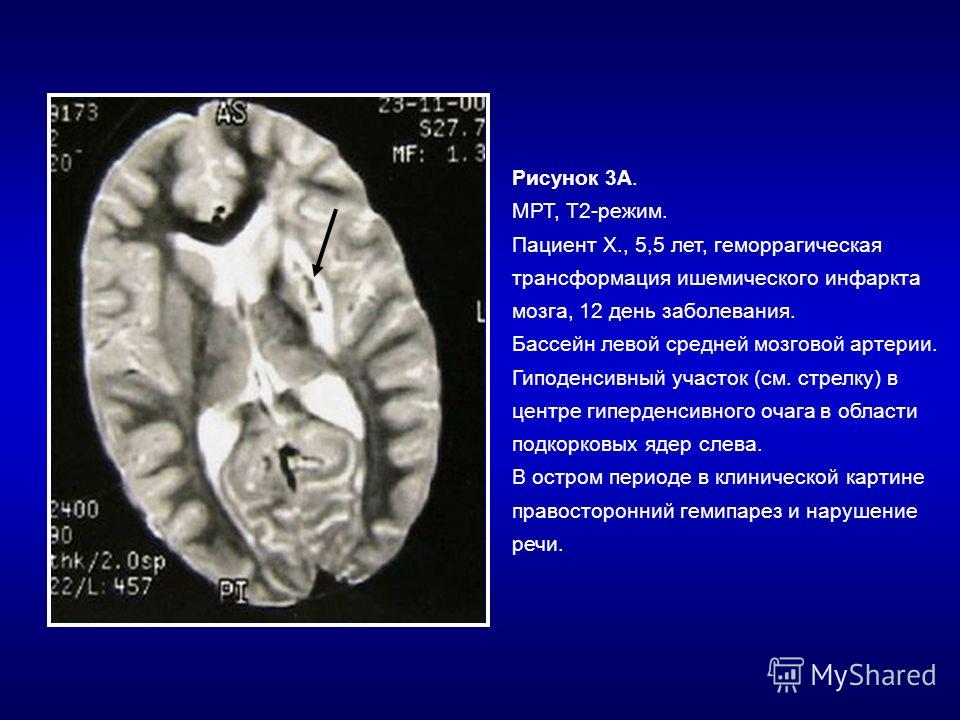

Иллюстрации и пояснения: гиподенсивный очаг на КТ головного мозга